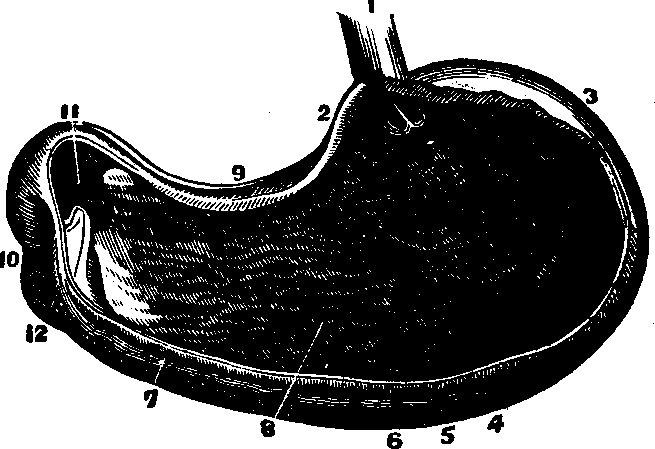

Fig. 28. A representation of the

interior of the stomach. 1. The esophagus. 2. Cardiac orifice

opening into the stomach. 6. The middle or muscular coat. 7.

The interior or mucous coat. 10. The beginning of the duodenum.

11. The pyloric orifice.

The Stomach is a musculo-membranous, conoidal sac, communicating with the esophagus by means of the cardiac orifice (see Fig. 28). It is situated obliquely with reference to the body, its base lying at the left side, while the apex is directed toward the right side. The stomach is between the liver and spleen, subjacent to the diaphragm, and communicates with the intestinal canal by the pyloric orifice. It has three coats. The peritoneal, or external coat is composed of compact, cellular tissue, woven into a thin, serous membrane, and assists in keeping the stomach in place. The middle coat is formed of three layers of muscular fibers: in the first, the fibres run [pg 40]longitudinally; in the second, in a circular direction; and in the third, they are placed obliquely to the others. The interior, or mucous coat, lines this organ. The stomach has a soft, spongy appearance, and, when not distended, lies in folds. During life, it is ordinarily of a pinkish color. It is provided with numerous small glands, which secrete the gastric fluid necessary for the digestion of food. The lining membrane, when divested of mucus, has a wrinkled appearance. The arteries, veins, and lymphatics, of the stomach are numerous.